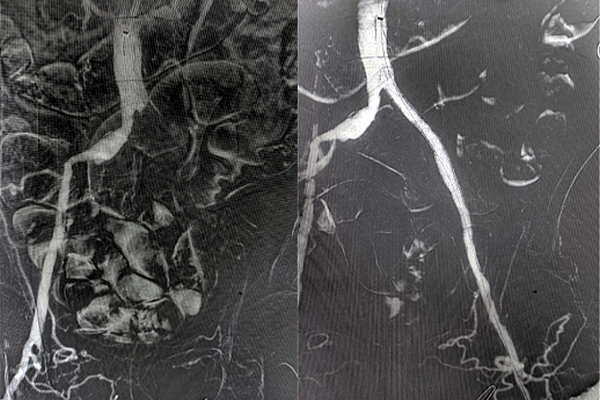

穿刺左侧肱动脉,入5F血管鞘,单弯导管配合超滑导丝超选择进入肠系膜上动脉,造影可见肠系膜上动脉主干血栓形成,更换8F长鞘至肠系膜上动脉开口处,入Indigo机械血栓抽吸系统,反复吸栓3次后,造影见肠系膜上动脉主干近端明显狭窄,后于狭窄处植入VBHR06050W覆膜支架系统,再次造影见肠系膜上动脉血流通畅。长鞘入腹主动脉远端,造影见左侧髂动脉血栓形成,入Indigo机械血栓抽吸系统,反复吸栓后,局部可见明显狭窄,于狭窄处给予球囊扩张后支架植入,造影见髂动脉血流通畅,术毕。郝大爷术后腹痛明显缓解,左下肢疼痛症状消失、皮温明显升高,现已康复出院。

术中造影